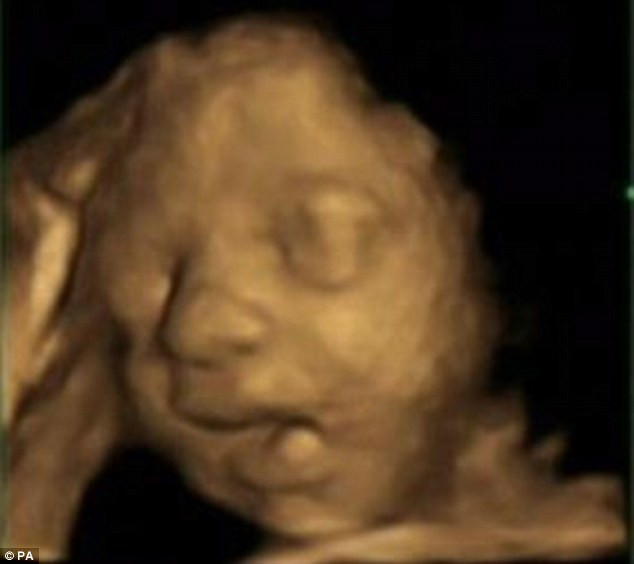

Anne karnındaki bebeğin esneme anları - Resim: 1

İngiltere’deki Durham Üniversitesi Psikoloji Departmanı’nın, sağlık ve bilim alanında önemli makalelere yer veren PLOS ONE dergisinde yayınlanan araştırma sonuçlarına göre, 15 sağlıklı bebekte görülen yarım ağız açma hareketinin ‘esneme’ olduğu belirlendi. Doğumdan önce bebeklerin hıçkırdıkları, yutkundukları ve gerindikleri biliniyordu. Ancak esnemeleri ilk kez bu kadar net bir şekilde tespit edildi. Esnemenin, bebeğin sağlığını gözlemlemede yeni ve önemli bir ipucu olacağı düşünülüyor.